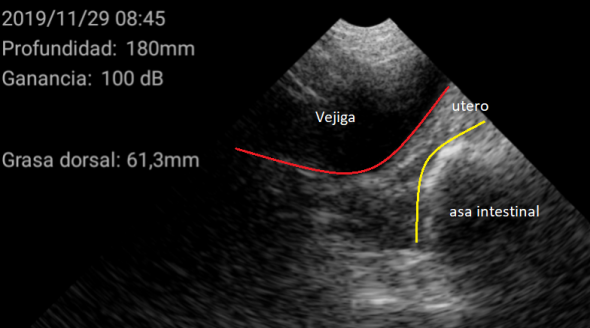

Al llegar a la granja y realizar las ecografías en las nulíparas se encontraron las siguientes imágenes captadas por el ecógrafo WiFi de KUBUS (figura 1).

Figura 1. Cerda impúber

Se considera cerda impúber, aquella que nunca ha presentado un celo, teniendo los ovarios inactivos con folículos de menos de 4mm de diámetro y con una medición del útero menor a 1 cm (figura 2).